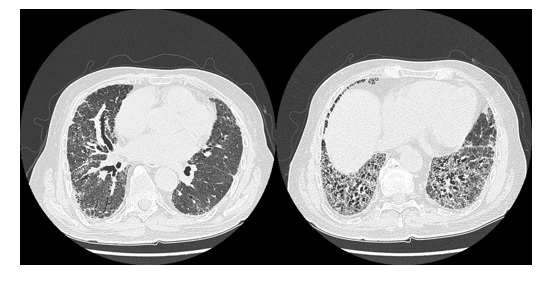

74-letni pacjent skierowany do poradni pneumonologicznej przez lekarza rodzinnego z rozpoznaniem nawracającego zapalenia płuc. Na podstawie wywiadu ustalono postępującą duszność wysiłkową, nikotynizm w wywiadzie 20-paczko lat. Choroby dodatkowe: nadciśnienie tętnicze dobrze kontrolowane. W ostatnim roku chory miał czterokrotnie podawane antybiotyki przez lekarza rodzinnego, lecz nigdy nie gorączkował. W badaniu fizykalnym stwierdzono obustronne metaliczne trzeszczenia nad dolnymi polami płucnym, w badaniach czynnościowych: FEV1/FVC 0,95; FEV1 35%N, FVC 28%N, TLC 32%N, DLCO 19,9 %N. Wykonano TK HRCT:

W oparciu o w/w: